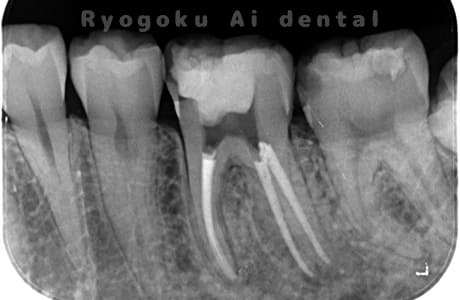

噛むと痛みが出る、とのことで来院した患者様です。他院での根管治療を終えてましたが、根尖病変を認めるため、マイクロエンドを行いました。